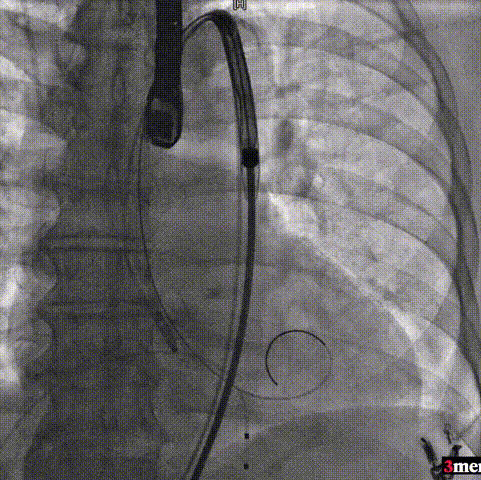

手术过程回顾:

患者全麻后,右侧股动脉建立主入路,主动脉根部造影显示主动脉瓣明显钙化。心室内轻微反流,主动脉及心脏情况整体较为稳定。直头导丝跨瓣后,在超硬导丝支撑下,瓣膜输送系统顺利跨瓣。在180次/分快速心室起搏下,确定降压至50mmHg后选择25mm球囊进行预扩张。根据术前评估及球囊预扩情况,最终选择直径29mm瓣膜进行植入。

主动脉根部造影

直头导丝跨瓣

球囊预扩

输送器过弓

输送器定位

瓣膜脱钩